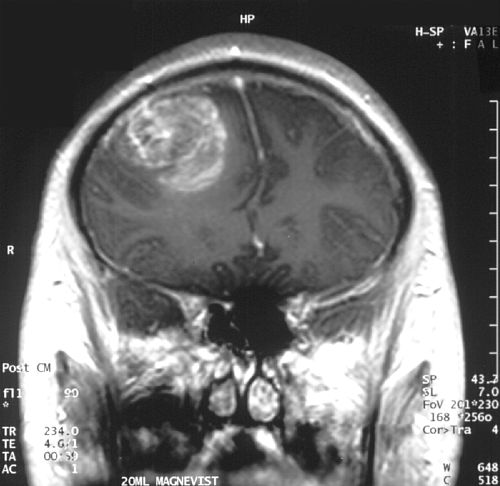

DiagnosisMagnetic resonance imaging; histopathology

Diagnostic workup centers on neuroimaging with contrast-enhanced magnetic resonance imaging performed at centers like Mount Sinai Hospital and King’s College Hospital, often supplemented by computed tomography in emergency settings at Royal London Hospital. Definitive diagnosis requires surgical biopsy or resection with neuropathological examination referencing criteria from the World Health Organization classification and laboratories at institutions such as Mayo Clinic and Johns Hopkins Hospital. Molecular testing for biomarkers including MGMT promoter methylation, IDH1 and IDH2 mutations, and 1p/19q codeletion is routinely performed in reference laboratories at University of Pennsylvania and Memorial Sloan Kettering Cancer Center to guide prognosis and therapy.